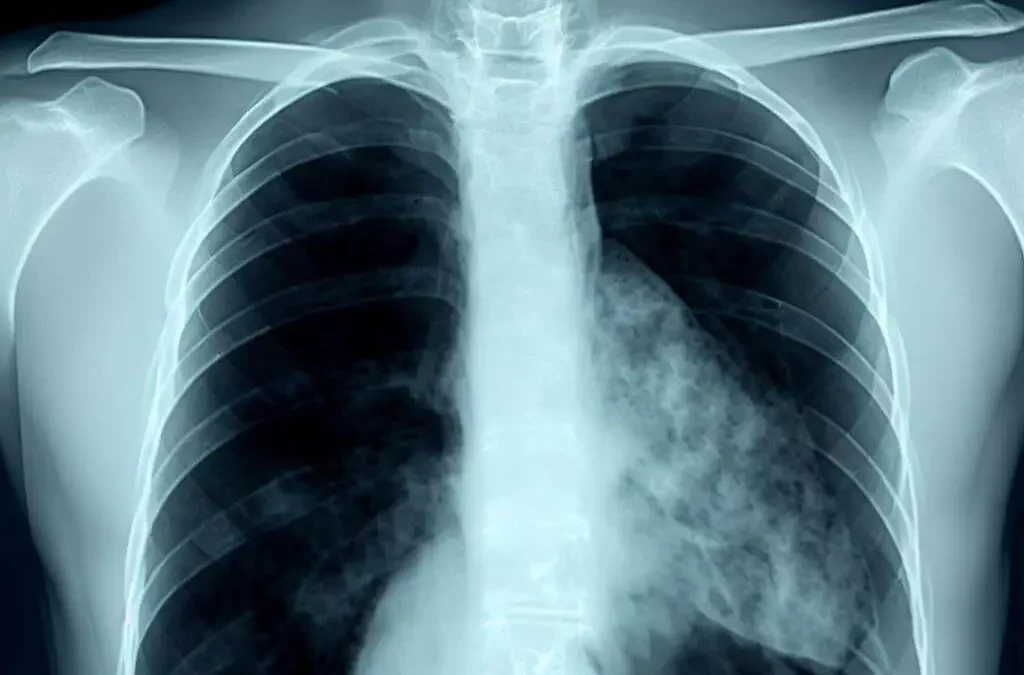

El impacto digital y en redes sociales del Día Mundial contra la Neumonía se hace sentir en Canarias

por MMI Analytics | Nov 11, 2022 | Informes Sectoriales, Salud

MMI Analytics realizó un seguimiento de medios sobre el Día Mundial contra la Neumonía – Imagen generada gracias a BingIA El 12 de noviembre se celebra el “Día Mundial contra la Neumonía” con el objetivo de sensibilizar a la población mundial sobre el problema...